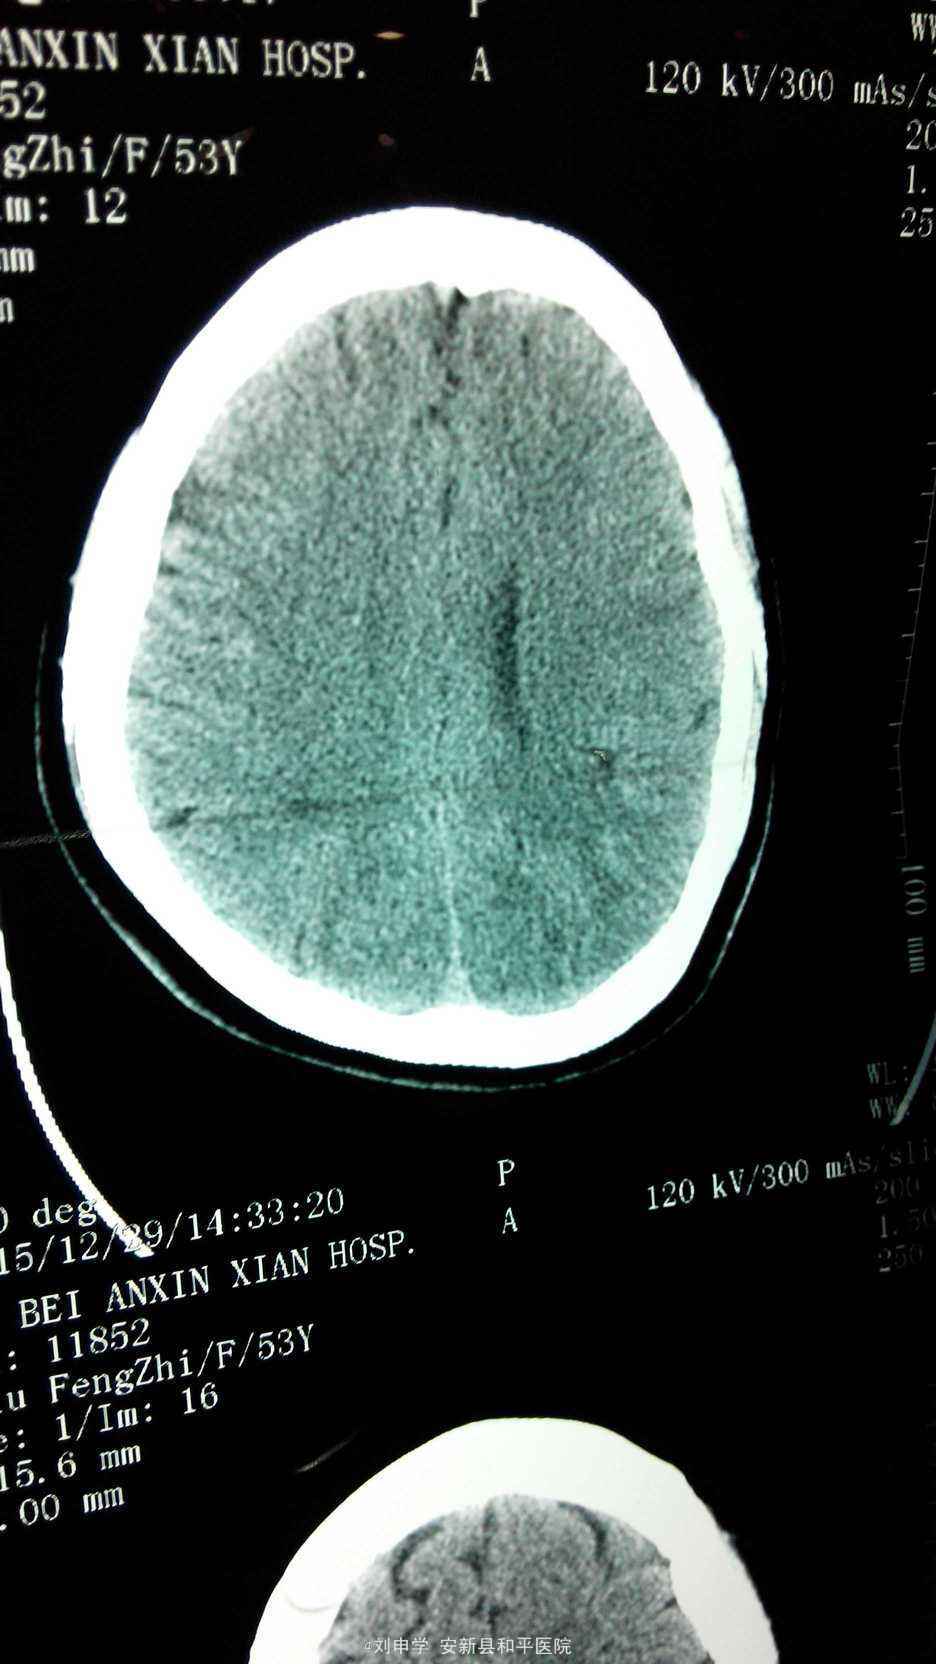

查体血压160/100mmHg, 神清,双侧瞳孔等大正园,对光反射正常,无偏盲,复视。心率56次./分,四肢肌力,肌张力正常,双巴氏征阴性。心电图:窦律心率56次/分。头颅CT提示左额叶顶叶脑梗塞。化验血脂正常。

入院初步诊断:1.脑梗塞,2.高血压。给予抗血小板,活血及营养脑细胞,调脂,降压等治疗。住院10天好转出院。